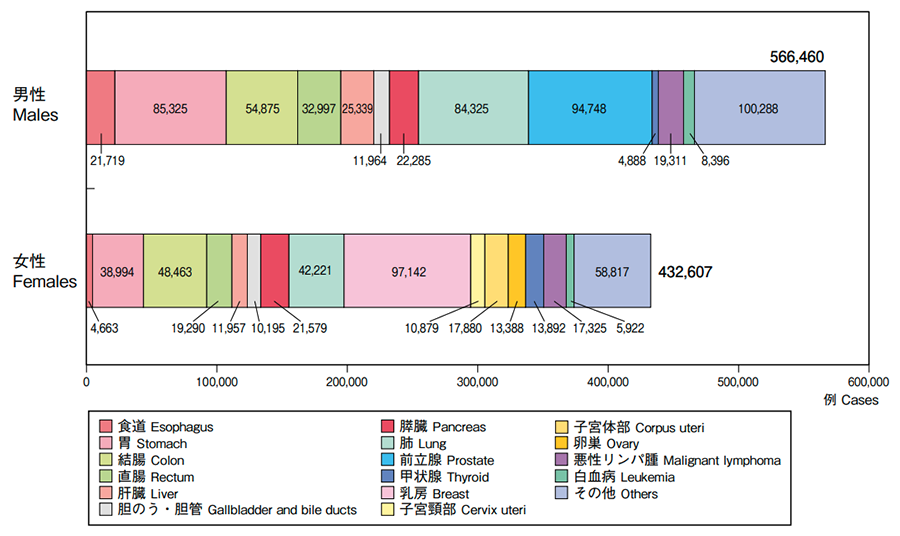

2021年の推計値では、日本のがん患者数は、約100万9,800人(男性約57万7,900人、女性約43万1,900人)です。部位別でみると、男性では前立腺がん(17%)、胃がん(16%)、大腸がん(15%)、肺がん(15%)、肝臓がん(5%)の順で多く、女性では乳がん(22%)、大腸がん(16%)、肺がん(10%)、胃がん(9%)、子宮がん(7%)の順で多くなっています。

また、同じく2021年のデータによると、がんによる死亡者の数は、約37万8,600人(男性約21万8,900人、女性約15万9,700人)と推計されています。部位別でみると、男性では肺がん(24%)が最も多く、次いで大腸がん(13%)、胃がん(12%)、膵臓がん(8%)、肝臓がん(7%)の順、女性では大腸がん(16%)が最も多く、肺がん(14%)、膵臓がん(12%)、乳がん(10%)、胃がん(9%)と続きます。

部位別予測がん罹患数(2021年)

部位別のがん患者数(2018年)